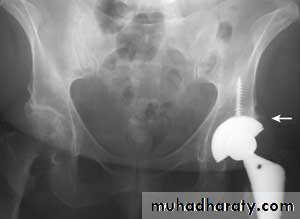

1- Arthroplasty: replacement of joint by prosthesis can be performed and give excellent results especially in hip and knee, other joints also can be replaced. ( articular surface of both side of joint resected and replaced by artificial joint). It provide painless mobile joint.2- Arthrodesis if stiffness not interfere with function like ankle and foots joints , (articular surface of both side of joint resected and the two bone fused to each other in physiological position). ). It provide painless stiff limb.